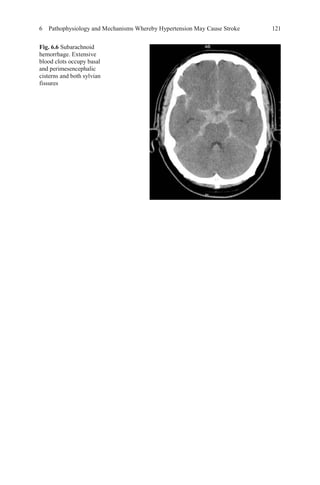

20. AmeryA, Birkenhäger W, Brixko P,et al. Mortality and morbidity from the European Working

Party on High Blood Pressure in the Elderly Trial. Lancet. 1985;1:1349–54.

21. MRC Trial of treatment of mild hypertension: principal results. Medical Research Council